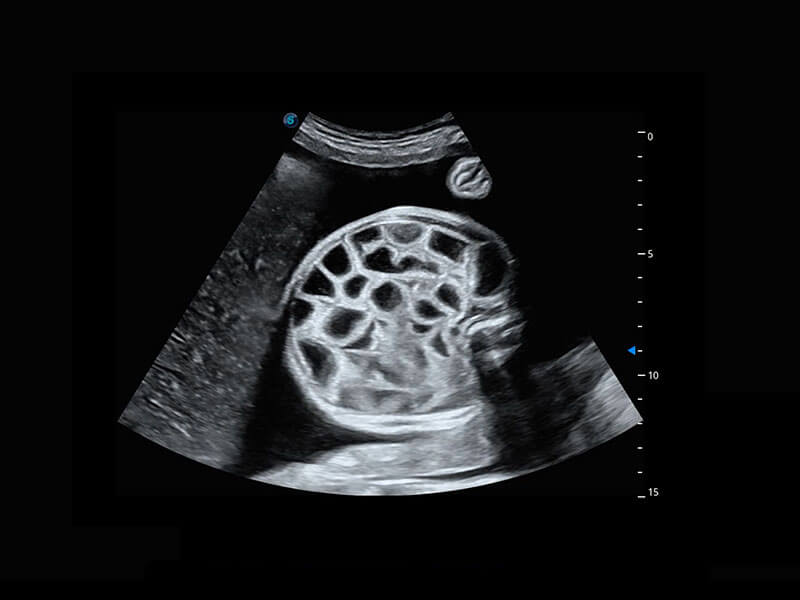

P60提供简单易学易用的高端诊断工具,为您中晚孕筛查提供快速清晰的解剖信息。

S-Fetus能够助您在实时扫查过程中自动识别标准切面、自动测量并录入报告。一个按键,即可快速、高效地获取胎儿生理指标,简化您的产科检查操作。